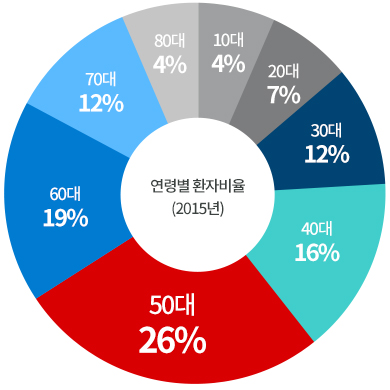

대상포진 환자추이